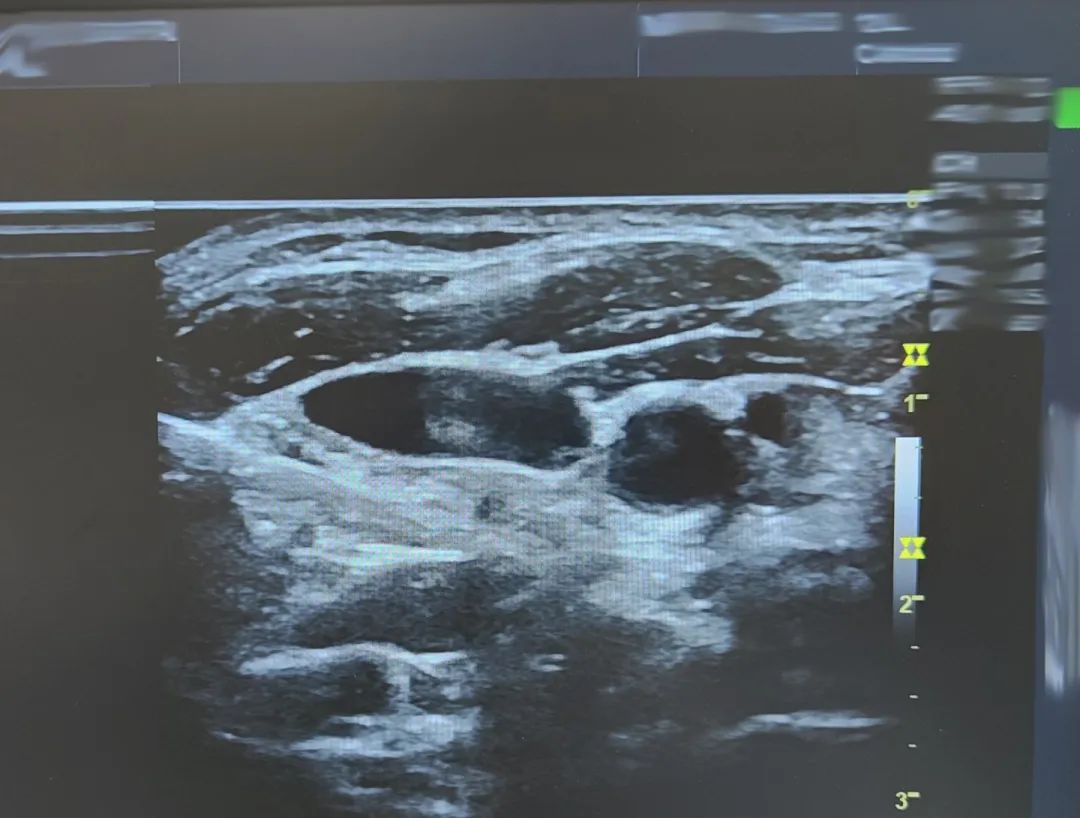

星状神经节阻滞(SGB)是一种常用的微创治疗方法,将局麻药注射在含有星状神经节的疏松结缔组织内以达到颈交感干、颈交感神经节与节前、节后神经及其支配范围的可逆性阻滞。能够让自主神经功能重新恢复到平衡状态,可以较全面地纠正失眠患者的睡眠结构,以及改善整个睡眠进程,例如可以缩短入睡的时间,可以减少睡眠过程中觉醒次数,以及觉醒时间,可以明显延长睡眠时长,提高睡眠质量,使一些就诊无门,多方治疗无效的患者看到了希望,不用再忍受由于神经内分泌失调带来的痛苦。